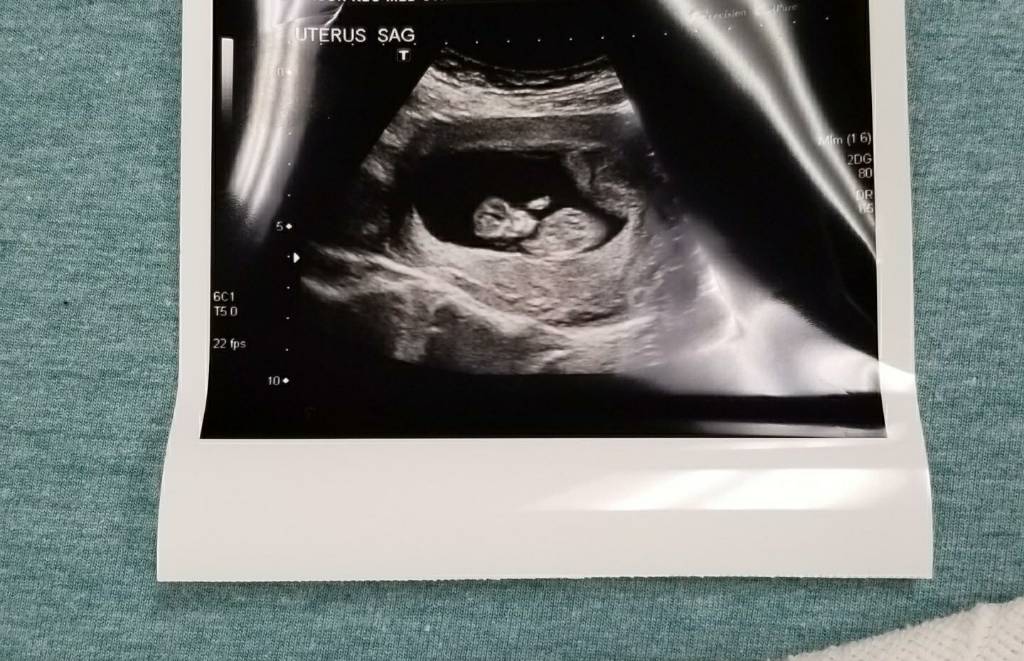

On bedrest with placenta previa...My 4th..Any guesses to gender by U/S pic?Attachment 37781

Way too early for guesses.